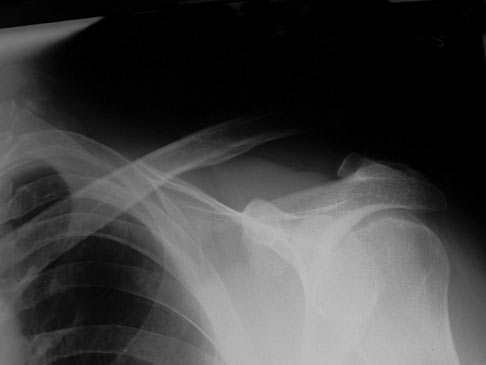

QUESTIONS 1 of 7 1 2 3 4 5 6 7 Previous Next Sorry, this question is for PEAK Premium Subscribers only Upgrade to PEAK You have 100% on this question. Just skip this one for now. Take This Question Anyway (OBQ09.272) A 58-year-old right-hand dominant accountant falls off a bicycle 4 days ago and injured his left non-dominant shoulder. A radiograph is shown in Figure A. The axillary radiograph shows no antero-posterior translation. What is the most appropriate next step in treatment? Review Topic QID: 3085 FIGURES: A Type & Select Correct Answer 1 Coracoclavicular ligament reconstruction 1% (35/2756) 2 Acromioclavicular capsular reconstruction 1% (21/2756) 3 Sling and early ROM exercises 97% (2668/2756) 4 Arthroscopic distal clavicle excision 0% (8/2756) 5 Weaver-Dunn procedure 1% (16/2756) L 1 Select Answer to see Preferred Response SUBMIT RESPONSE 3 Sorry, this question is for PEAK Premium Subscribers only Upgrade to PEAK You have 100% on this question. Just skip this one for now. Take This Question Anyway (OBQ08.7) For Grade III AC joint separations, surgical treatment results in which of the following when compared to non-operative management? Review Topic QID: 393 Type & Select Correct Answer 1 Faster return to play 18% (324/1835) 2 Increased range of motion 3% (55/1835) 3 Increased functional rotator cuff strength 5% (89/1835) 4 Decreased funtional rotator cuff strength 0% (5/1835) 5 Higher complication rate 74% (1353/1835) L 2 Select Answer to see Preferred Response SUBMIT RESPONSE 5 You have 100% on this question. Just skip this one for now. Take This Question Anyway (OBQ08.203) A football player sustains a suspected shoulder separation. In addition to a true AP and an axillary lateral, which of the following additional radiographic views is most appropriate to evaluate the AC joint? Review Topic QID: 589 Type & Select Correct Answer 1 Stryker notch view 5% (67/1247) 2 West Point view 7% (90/1247) 3 Supraspinatus outlet view 4% (46/1247) 4 Velpeau view 5% (62/1247) 5 Zanca view 78% (978/1247) L 2 Select Answer to see Preferred Response SUBMIT RESPONSE 5 You have 100% on this question. Just skip this one for now. Take This Question Anyway This is an AAOS Self assessment question. Orthobullets was not involved into the editorial process, and does not have the ability to alter. If you prefer to hide SAE questions on topics simply turn them off in your Content Settings (SAE07SM.86) A 46-year-old woman fell from her bicycle and sustained the injury shown in Figure 24. Which of the following ligaments has been disrupted? Review Topic QID: 8748 FIGURES: A Type & Select Correct Answer 1 Acromioclavicular 1% (8/655) 2 Acromioclavicular and coracoclavicular 96% (627/655) 3 Coracoclavicular 3% (17/655) 4 Coracoacromial and sternoclavicular 0% (2/655) 5 Sternoclavicular 0% (0/655) L 1 Select Answer to see Preferred Response SUBMIT RESPONSE 2 You have 100% on this question. Just skip this one for now. Take This Question Anyway (OBQ05.251) What is the preferred treatment for a symptomatic acute acromioclavicular separation where there is a 20% increase in the coracoclavicular distance on AP radiograph compared to the opposite uninjured side? Review Topic QID: 1137 Type & Select Correct Answer 1 Anatomic coracoclavicular ligament reconstruction 3% (58/1677) 2 Acute repair of acromioclavicular capsule 1% (10/1677) 3 Sling followed by early physical therapy 94% (1572/1677) 4 Reduction and retrograde pinning of the acromioclavicular joint 1% (21/1677) 5 Distal clavicle excision 0% (5/1677) L 1 Select Answer to see Preferred Response SUBMIT RESPONSE 3

Introduction Definition injury to the acromioclavicular (AC) joint with disruption of the AC ligaments with or without coracoclavicular (CC) ligament disruption Epidemiology incidence common injury making up 9% of shoulder girdle injuries demographics more common in males and athletes Pathophysiology mechanism direct blow to the shoulder often sustained while falling onto the shoulder Anatomy Osteology diarthrodial joint articulation of the scapula (medial acromion) and the lateral clavicle oblique orientation of joint surface contains a fibrocartilaginous intraarticular disc between the osseous elements analogous to the meniscus of the knee involutes with age, disintegrates by age 40 Motion primarily gliding motion rotational motion is minimal clavicle rotates 40-50° posteriorly with shoulder elevation only ~8° rotation through the AC joint, due to synchronous scapuloclavicular motion Stability static joint capsule acromioclavicular (AC) ligaments controls horizontal motion and anterior-posterior stability has superior, inferior, anterior and posterior components posterior and superior AC ligaments are most important for stability coracoclavicular (CC) ligaments controls vertical motion and superior-inferior stability two ligaments conoid medial inserts on clavicle 4.5cm medial to lateral edge most important for vertical stability trapezoid lateral inserts on clavicle 3cm medial to lateral edge dynamic anterior deltoid trapezius Presentation Symptoms pain usually over AC joint can also be referred to the trapezius Physical exam lateral clavicle or AC joint tenderness abnormal contour of the shoulder compared to contralateral side stability assessment horizontal (anterior-posterior) stability evaluates AC ligaments cross-body adduction horizontal instability (ISAKOS type 3B) may indicate need for more aggressive treatment vertical (superior-inferior) stability evaluates CC ligaments Imaging Radiographs required views bilateral anteroposterior (AP) view of AC joints compare displacement to contralateral side measured as distance from top of coracoid to bottom of clavicle use 1/3 penetration on AP to visualize AC joint axillary lateral view required to diagnose Type IV (posterior) zanca view performed by tilting the x-ray beam 10-15° cephalad and using only 50% of the standard shoulder AP penetrance additional veiws cross-body adduction view (Basmania) scapular Y performed with cross-body adduction stress weighted stress views usually no longer used may help differentiate Type II from Type III findings fractures can mimic AC separations base of coracoid fracture Neer type 2A distal clavicle fracture ligaments remain attached to distal fragment as proximal (medial) fragment displaces Classification Rockwood Classification Type AC ligament CC ligament Exam Radiographs Reducibility Treatment Illus. Xray Type I sprain normal AC tenderness; no AC instability normal sling Type II torn sprain AC horizontal instability AC joint disrupted; increased CC distance < 25% of contralateral reducible sling Type III torn torn increased CC distance 25-100% of contralateral reducible controversial IIIA AC vertical instability, no horizontal stability IIIB AC vertical + horizontal instability Type IV torn torn skin tenting, posterior fullness lateral clavicle displaced posterior through trapezius on the axillary lateral XR not reducible surgery Type V torn torn severe shoulder droop, does not improve with shrug increased CC distance > 100% of contralateral not reducible surgery Type VI torn torn rare; associated injuries; paresthesias inferior dislocation of lateral clavicle, lying either in subacromial or subcoracoid position not reducible surgery Differential Diagnosis Coracoid fracture base of coracoid fracture can mimic a CC ligament disruption has superiorly displaced distal clavicle, but normal CC distance (normal is 11-13mm) Distal clavicle fracture (Neer 2A) can mimic AC separations as well, as ligaments remain attached to distal component Treatment Nonoperative brief sling immobilization, rest, ice, physical therapy indications type I and II type III in most individuals good results when clavicle displaced < 2cm rehab early shoulder range of motion regain functional motion by 6 weeks return to normal activity at 12 weeks consider corticosteroid injections outcomes type III treated non-op had higher DASH scores at 6 weeks and 3 months, and equal function at 1 year with lower rate of secondary surgery (removal of hardware) compared to those treated operatively complications AC joint arthritis chronic subluxation and instability Operative CC interval restoration (ORIF vs. Ligament Reconstruction) indications acute type IV, V or VI injuries acute type III injuries in laborers, elite athletes, patients with cosmetic concerns chronic type III injuries that failed non-op treatment historically it was thought acute injuries were treated with ORIF and chronic injuries were treated with CC ligment reconstruction however, new studies have shown no difference in outcomes in types III injuries treated surgically with ORIF after 6 weeks non-op treatment versus immediate surgery contraindications patient unlikely to comply with postoperative rehabilitation skin problems over fixation approach site techniques ligament reconstruction with soft tissue graft Modified Weaver-Dunn distal clavicle excision with transfer of coracoacromial ligament to the distal clavicle to recreate CC ligament autograft allograft fixation suture hook plate CC screw (Bosworth) cortical flip button (e.g Dog Bone)(+/- arthroscopic assistance) K-wire rehabilitation sling immobilization for 6 weeks, no shoulder range of motion return to full activity after 6 months Techniques ORIF with CC screw fixation (Bosworth screw) has fallen out of favor approach proximal aspect of anterolateral approach to the shoulder technique screw placement from distal clavicle to coracoid, superior to inferior pros rigid internal fixation cons danger of screw being too long and damage to critical structure below coracoid routine screw removal at 8-12 weeks is advised to prevent screw breakage due to normal motion between clavicle and scapula complications hardware irritation at level of screw purchase in coracoid hardware failure at level of screw purchase in coracoid ORIF with CC suture fixation approach proximal aspect of anterolateral approach to the shoulder technique suture placed either around or through clavicle and around the base of the coracoid can also use suture anchors for coracoid fixation pros no risk of hardware failure or migration cons suture not as strong as screw fixation requires careful suture passage inferior to coracoid due to proximity of crucial neurovascular structures complications suture erosion causing distal third clavicle fracture hardware irritation ORIF with AC pin fixation (Phemister Technique) approach can be done percutaneously technique smooth wire or pin fixation directly across AC joint cons hardware irritation complications high incidence of pin migration generally not performed due to high complication rates ORIF with AC hook plate fixation approach exposure of distal and middle clavicle technique use of standard hook plate over superior distal clavicle pros rigid fixation cons requires second surgery for plate removal complications acromial erosion hook pullout CC ligament reconstruction with coracoacromial (CA) ligament (Modified Weaver-Dunn) approach proximal aspect of anterolateral approach to the shoulder arthroscopic technique also described technique distal clavicle excision transfer of coracoacromial ligament to the distal clavicle to recreate CC ligament reinforce with internal fixation cons coracoacromial ligament only 20% as strong as normal CC ligament lack of internal fixation risks failure of soft tissue repair CC ligament reconstruction with free tendon graft approach proximal aspect of anterolateral approach to the shoulder can be performed arthroscopically-assisted graft autograft palmaris longus semitendinosus allograft tibialis anterior technique figure-of-eight passage of graft, looping around coracoid and fixation through clavicular tunnels reinforce with internal fixation pros graft reconstruction more closely recreates strength of native CC ligament cons standard risks of allograft use or autograft harvest lack of internal fixation risks failure of soft tissue repair Complications Residual pain at AC joint 30-50% AC arthritis more common with surgical management than with nonoperative treatment Hardware failure CC screw breakage/pullout Coracoid fracture can occur with coracoid tunnel drilling